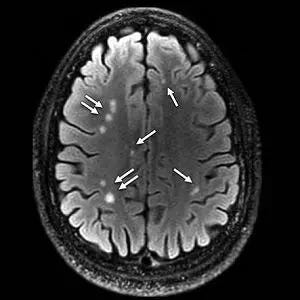

Intuitively it makes sense that statins would prevent dementia because they lower cholesterol and lipids and thus protect blood vessels from becoming clogged or bursting. About 75% of your cholesterol is made by your body, not consumed through diet, and statins prevent your liver from making as much cholesterol. When blood vessels become clogged by fats and cholesterol, small areas of the brain lose blood supply and oxygen, and this causes the neurons in that area to become damaged and the immune cells in that area to become inflamed. Micro-strokes from clogged or leaking small blood vessels in the brain cause one of the most common types of dementia, vascular dementia, and contribute to other types of dementia including Alzheimer’s. Areas of damage and micro-strokes can be seen on MRI and will be in your white matter hyper-intensities report if you have had the NeuroAge/BrainKey MRI test. White matter hyperintensities may be, to some extent, reversible with therapeutics and/or lifestyle interventions, especially if caught early. We suggest that you track them over time for this reason.